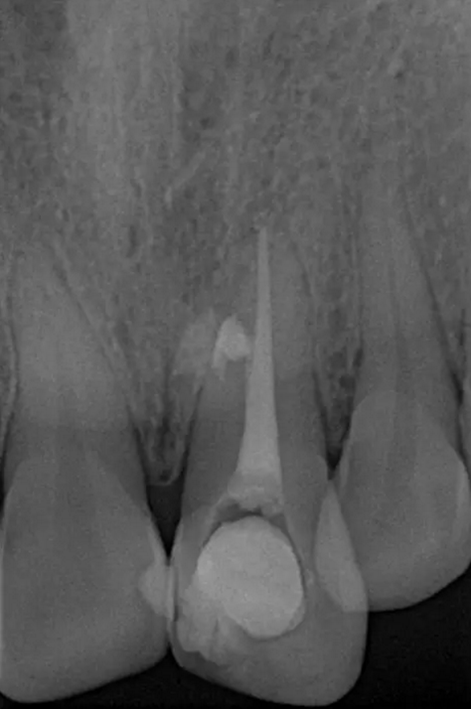

術(shù)前診斷片

患者女,年齡35左右,牙位21,根管治療曾經(jīng)歷過外院四到五次等不同地方的處理,還是不能咬硬物,會(huì)有酸、軟、痛的情況出現(xiàn),偶有自發(fā)疼痛,2016年9月初,轉(zhuǎn)診至我處治療21。術(shù)前拍片發(fā)現(xiàn)根中部存在側(cè)穿,橡皮障下常規(guī)再治療,隨后減輕了軟和痛的情況。因?yàn)閭?cè)穿,牙周膜受到牙膠尖等異物的持續(xù)刺激,酸軟的情況還是持續(xù)存在,所以決定行根尖外科手術(shù),采用MTA修補(bǔ)穿孔點(diǎn)。術(shù)后觀察半年左右,所有癥狀消除后,隨后熱牙膠充填。